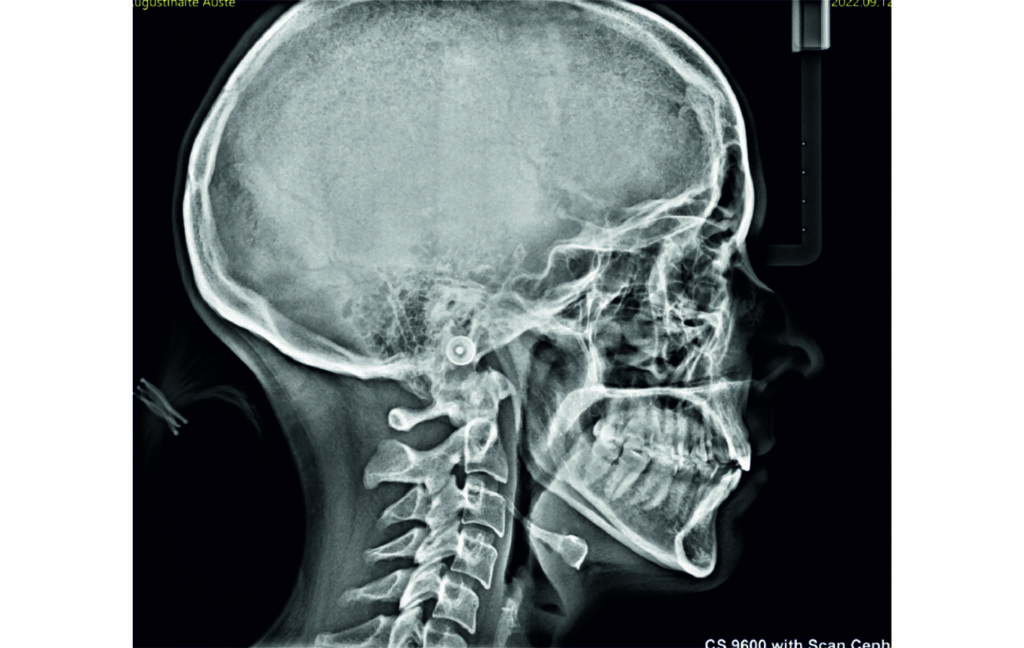

Angle Class II 2mm on the right, Angle Class II 2mm on the left, light mandibular asymmetry to the right, lower central line 1mm to the right, upper central line 1,5mm to the left, 1mm overjet and overbite. Sagittal asymmetry of upper dental arch. Light crowding upper and lower frontal segments, severe attrition of posterior teeth, night bruxism. Normal sagittal position of both jaws, high angle case, steep mandibular ramus,excessive lower facial height, open bite tendency.

Soft Tissue Analysis: convex profile, lower third of the face increased, slightly retrusive upper and lower lips, lip strain on closure.